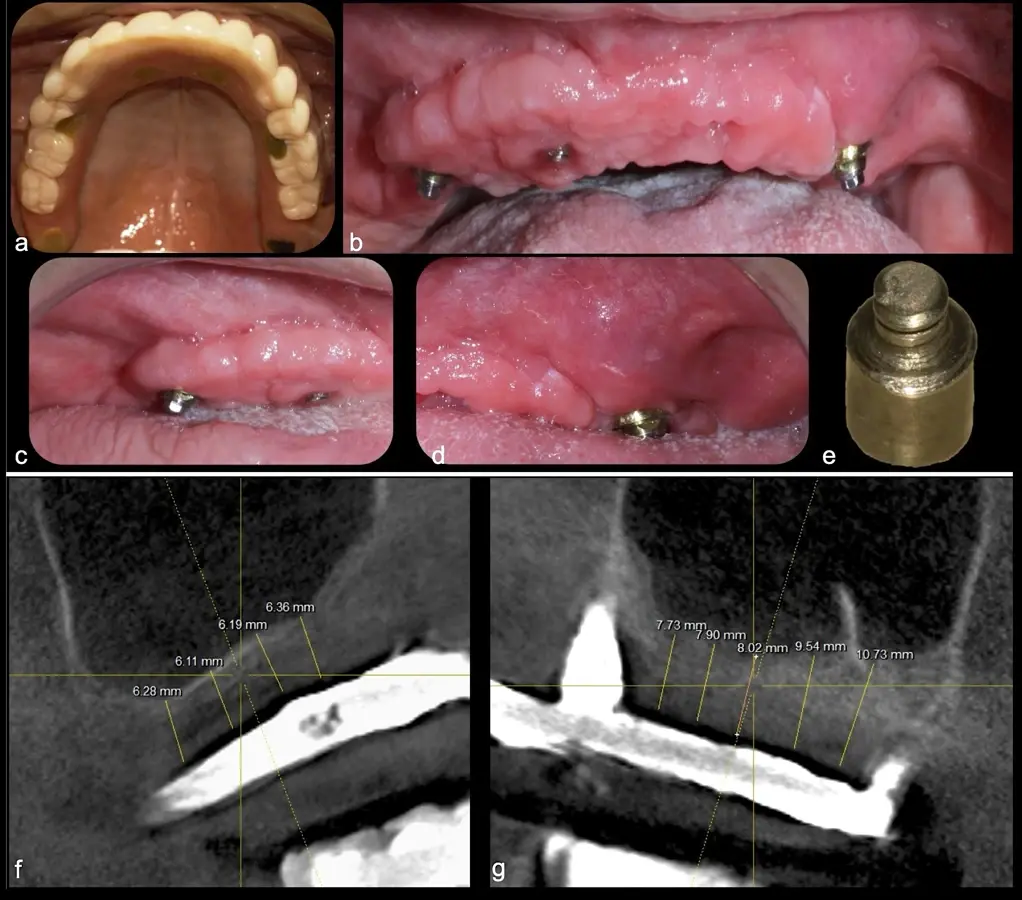

La técnica se inicia con la colocación de anestesia infiltrativa, posteriormente se realiza una incisión crestal o paracrestal con posibles liberantes verticales que deben de estar alejadas por lo menos 5 mm de los límites de la futura ventana y sobrepasar la línea mucogingival. Se realiza una elevación de colgajo, se inicia la antrostomía y antroplastía. Para ello, se emplea el inserto redondo diamantado de corte al momento de delimitar los bordes de la ventana de acceso. Luego se cambia al inserto aserrado liso de calibre fino con superficie diamantada, para profundizar y eliminar el hueso en el contorno de la ventana. Una vez que se traslucen los tejidos, se puede optar por el retiro de la tapa ósea o el levantamiento de ésta junto con la membrana.

Se inicia la elevación de la membrana de Schneider con el inserto redondeado no cortante en forma de disco, empleando movimientos suaves. El levantamiento puede complementarse con elevadores convencionales, siguiendo la dirección mesiodistal. La fase de desprendimiento inicia con el piso y sigue hacia la pared mesial para terminar, y de ser necesario, hacia la pared posterior. Existen diversos insertos con angulaciones y longitudes para mayor accesibilidad16 (Figura 1).

El tipo de inserto a ser utilizado dependerá del espesor de la pared ósea. Si la pared es menor a 0.5 mm, es mejor utilizar insertos de desgaste para prevenir la ruptura de la membrana de Schneider; si el espesor es mayor a 0.5 mm, se puede utilizar insertos de corte de espesor medio (Figura 3).

Una vez elevado el piso sinusal según la planificación se realiza la evaluación clínica de la integridad de la membrana y de posibles desgarros a través de la maniobra de Valsalva.24 Consiste en pedir al paciente que respire profundamente y retenga el aire, cerrar la boca, apretar la nariz con los dedos y forzar la salida de aire. Al final de la prueba, es necesario mantener la presión entre 10 a 15 segundos. Se identificará la movilidad de la membrana y la ausencia de burbujas de aire para corroborar que no hay perforaciones. Dependiendo de la decisión clínica se puede optar por adicionar en la superficie de la membrana de Schneider membranas de colágeno o de plasma rico en fibrina (PRF) para dar mayor soporte durante la inserción del biomaterial de relleno óseo (Figura 10).